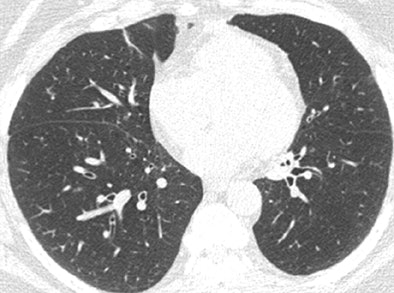

| Axial CT scans in two subjects with different COPD phenotypes: emphysema-predominant COPD (≥ 35% emphysema, <1.75-mm segmental bronchial wall thickness) (above) and airway-predominant COPD (<35% emphysema, ≥ 1.75-mm segmental bronchial wall thickness) (below). Images republished with permission of the Radiological Society of North America, from Radiology, July 25, 2011, 110173. |

In addition, while many patients had a mixture of structural changes related to their COPD, two subgroups predominantly with emphysema or large airway disease could be identified.

Patients with more than 35% emphysema volume and wall thickness greater than 1.75 mm had a higher COPD exacerbation frequency than did the subjects with less than 35% emphysema and a wall thickness of less than 1.75 mm.

The less-severe patients in both groups reported experiencing a mean of 0.62 exacerbation per year, compared with means of 1.1 exacerbations per year reported by the emphysema-predominant group (p < 0.0001) and 0.8 exacerbation per year reported by the airway-predominant group (p = 0.07).